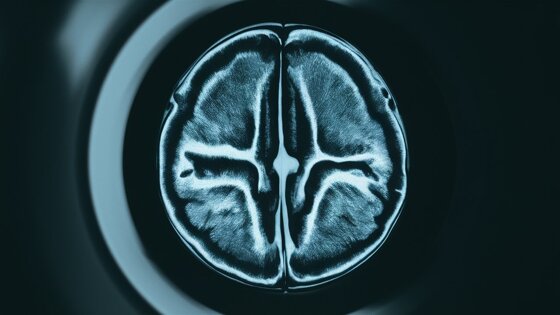

Ученые Технического университета Граца разработали метод, который позволяет получать точные изображения сердцебиения в реальном времени с помощью ограниченного объема данных МРТ. Эта работа, опубликованная в журнале Magnetic Resonance in Medicine, обещает значительно упростить процесс медицинской визуализации.

Используя продвинутые нейронные сети и методы самообучения, международная команда ученых смогла создавать четкие МРТ-изображения даже без идеальных тренировочных данных. Система делит исходные измерения на две части: одна используется для восстановления изображения, а вторая помогает проверять точность реконструкции.

Разработка не только ускорит процессы, но и снизит затраты на диагностику, обеспечивая радиологов точными данными для анализа. Алгоритмы и данные МРТ доступны для свободного использования, что позволит другим исследователям воспроизводить результаты и развивать новую методику.